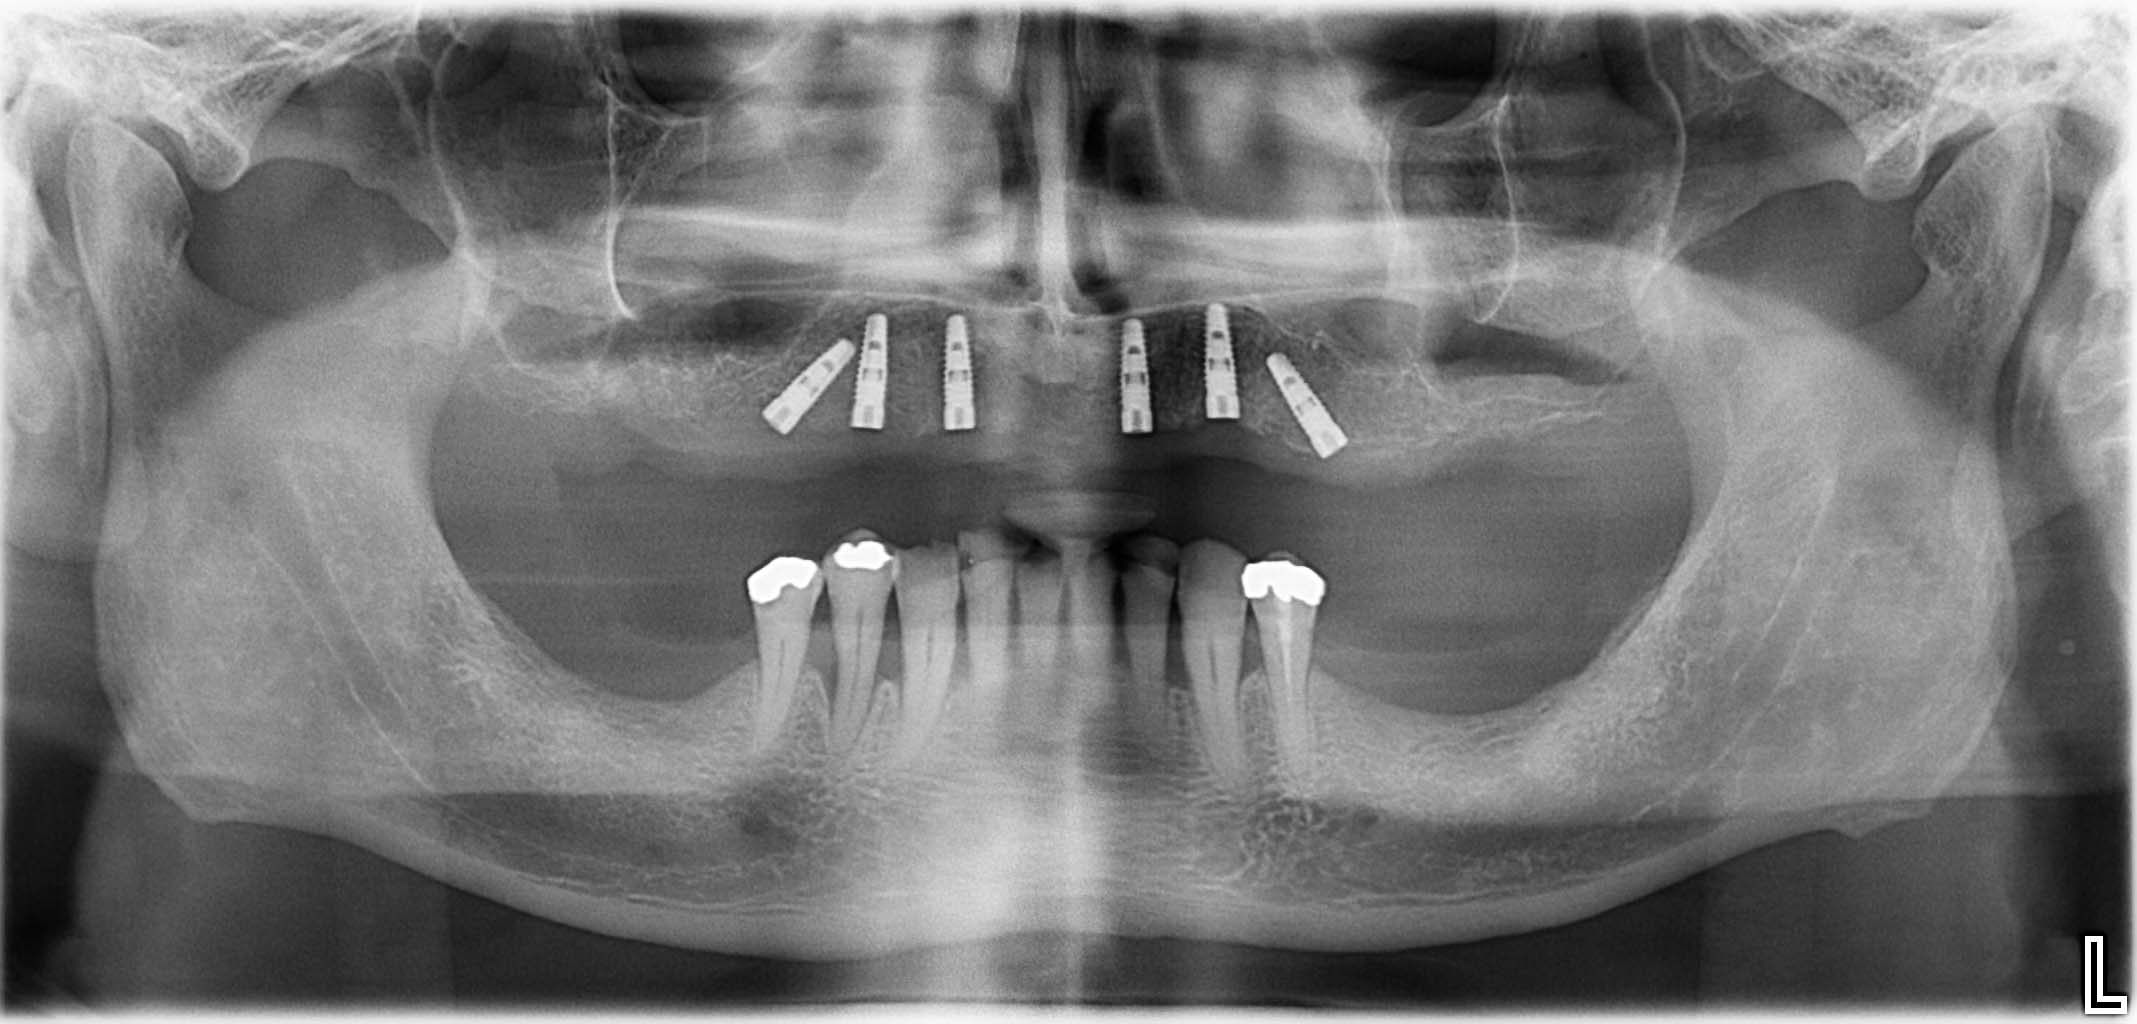

Erfolgreich implantierte Patientenfälle (klinische Fotos)